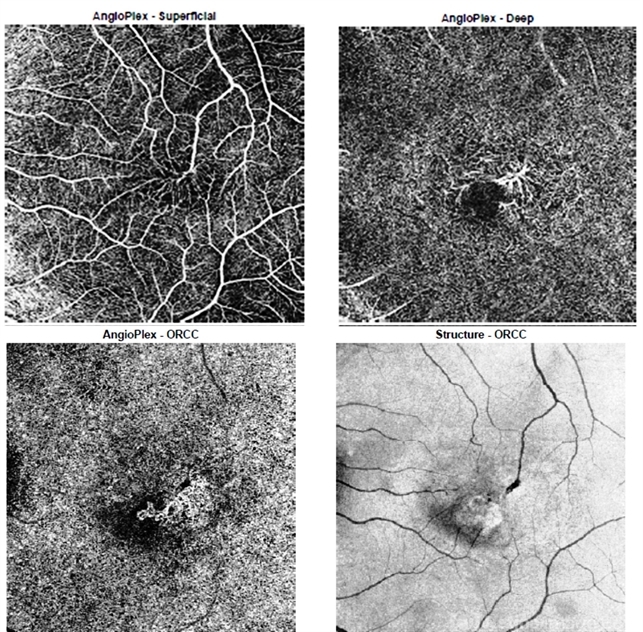

- macular telangiectasia type 2, optical coherence tomography (OCT)

- OCT-angiographic images of a 52-year-old gentlemen showing abnormal telangiectatic vessels over the macula in superficial layer which can be traced down to the deeper layer of capillaries. The outer retinal slab on OCTA delineates CNVM (a known complication of mactel). The structural image on extreme down right also shows the right-angled vessel (characteristic of mactel's and the associated structural damage secondary to CNV.